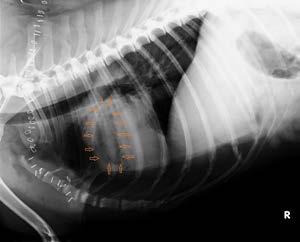

Post-mortem thoracic radiographs were performed. They showed an elliptical radiolucent focus measuring approximately 7cm in height and 3.5cm in length superimposed over the region of the right ventricle in lateral views (Figures 2 and 3).

The clinical presentation and thoracic radiographs support a diagnosis of venous air embolism.

In this unfortunate case, the iatrogenic rent in the axillary vein allowed air to enter the central venous system down a gravitational gradient to the right side of the heart. This resulted in outflow obstruction to the right ventricle, hypocapnia, hypoxaemia, hypotension, reduced cardiac output and ultimately cardiac arrest.

Figure 2. Lateral thoracic radiograph showing air in right ventricleThere are no minimally invasive aids with high sensitivity and specificity for diagnosing VAE. Transoesophageal echocardiography is the most sensitive technique for detecting VAE, being able to detect 0.02mL/kg of air. Precordial doppler ultrasound is another sensitive technique for detecting VAE, whereby the anaesthetist listens for a characteristic ‘drum-like’ or ‘mill-wheel’ murmur associated with VAE.